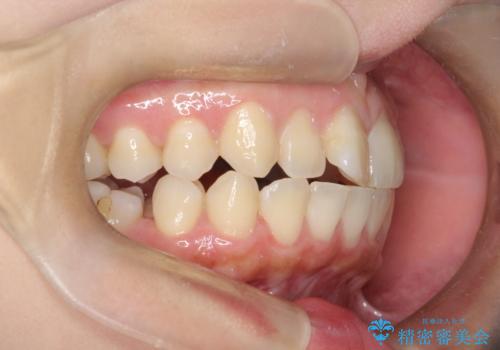

右下第二小臼歯の舌側転移の改善

- 患者様は、右下第二小臼歯が舌側に転移していることが主訴でした。診断の結果、抜歯を伴う矯正治療も検討しましたが、奥歯の遠心移動とIPR(インタープロキシマルリダクション)を行うことで、非抜歯で矯正を進めることが可能であると判断しました。治療計画では、審美ワイヤーを用いた2年間の治療で、歯列を整えつつ、臼歯関係や正中のバランスを維持しながら進めました。

非抜歯矯正では、歯の動きを慎重に調整することが求められます。本症例では、奥歯を遠心に移動させることで、舌側に転移した右下第二小臼歯の位置を改善しました。また、IPRを行うことで歯間スペースを確保し、無理なく歯列の調整を行いました。非抜歯での治療は、特に臼歯関係や正中を保ちながら治療できるというメリットがあり、最終的にはバランスの取れた歯並びを実現できました。審美ワイヤーを使用したことで、治療中も目立ちにくく、患者様の見た目にも配慮した治療を行いました。